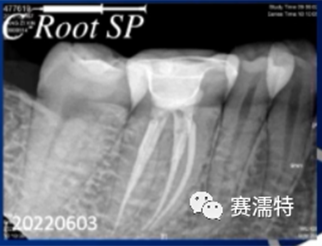

C-Root SP是預混合的、可即刻應用的、可注射的、遇水凝固的硅酸鹽類生物活性陶瓷糊劑材料,主要成分為硅酸鍶、氧化鋯、磷酸鈣、氫氧化鈣,用于根管的密封和永久充填,適合單尖法、側壓法和熱牙膠法。 C-Root SP為世界口腔醫生提供一個“鍶生物陶瓷”的新選擇! >>>